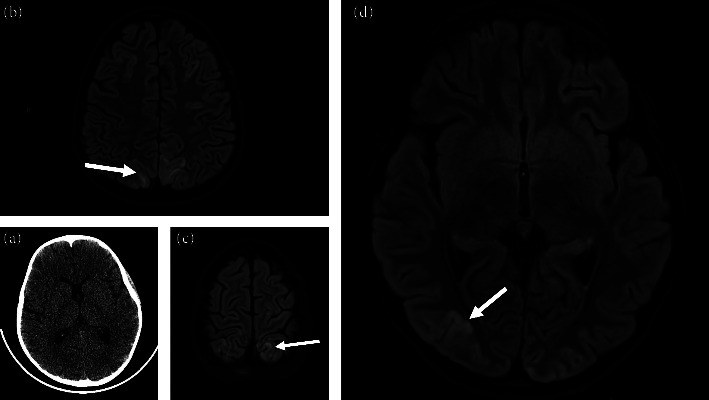

In this article, we describe a novel case of SARS-CoV-2-associated-hemophagocytic lymphohistiocytosis (HLH) complicated by posterior reversible encephalopathy syndrome (PRES). Initially diagnosed with multisystem inflammatory response in children (MIS-C), the patient received a large corticosteroid dose days before the onset of neurological symptoms. After developing PRES, the patient was treated with antihypertensives, antiepileptics, dexamethasone, and anakinra, leading to neurologic normalization. We propose that given the challenging diagnostic picture of PRES developing in patients with HLH or MIS-C, institutionalized standards for blood pressure management during corticosteroid induction may significantly improve outcomes in patients being treated for hyperinflammatory syndromes who develop neurological symptoms.